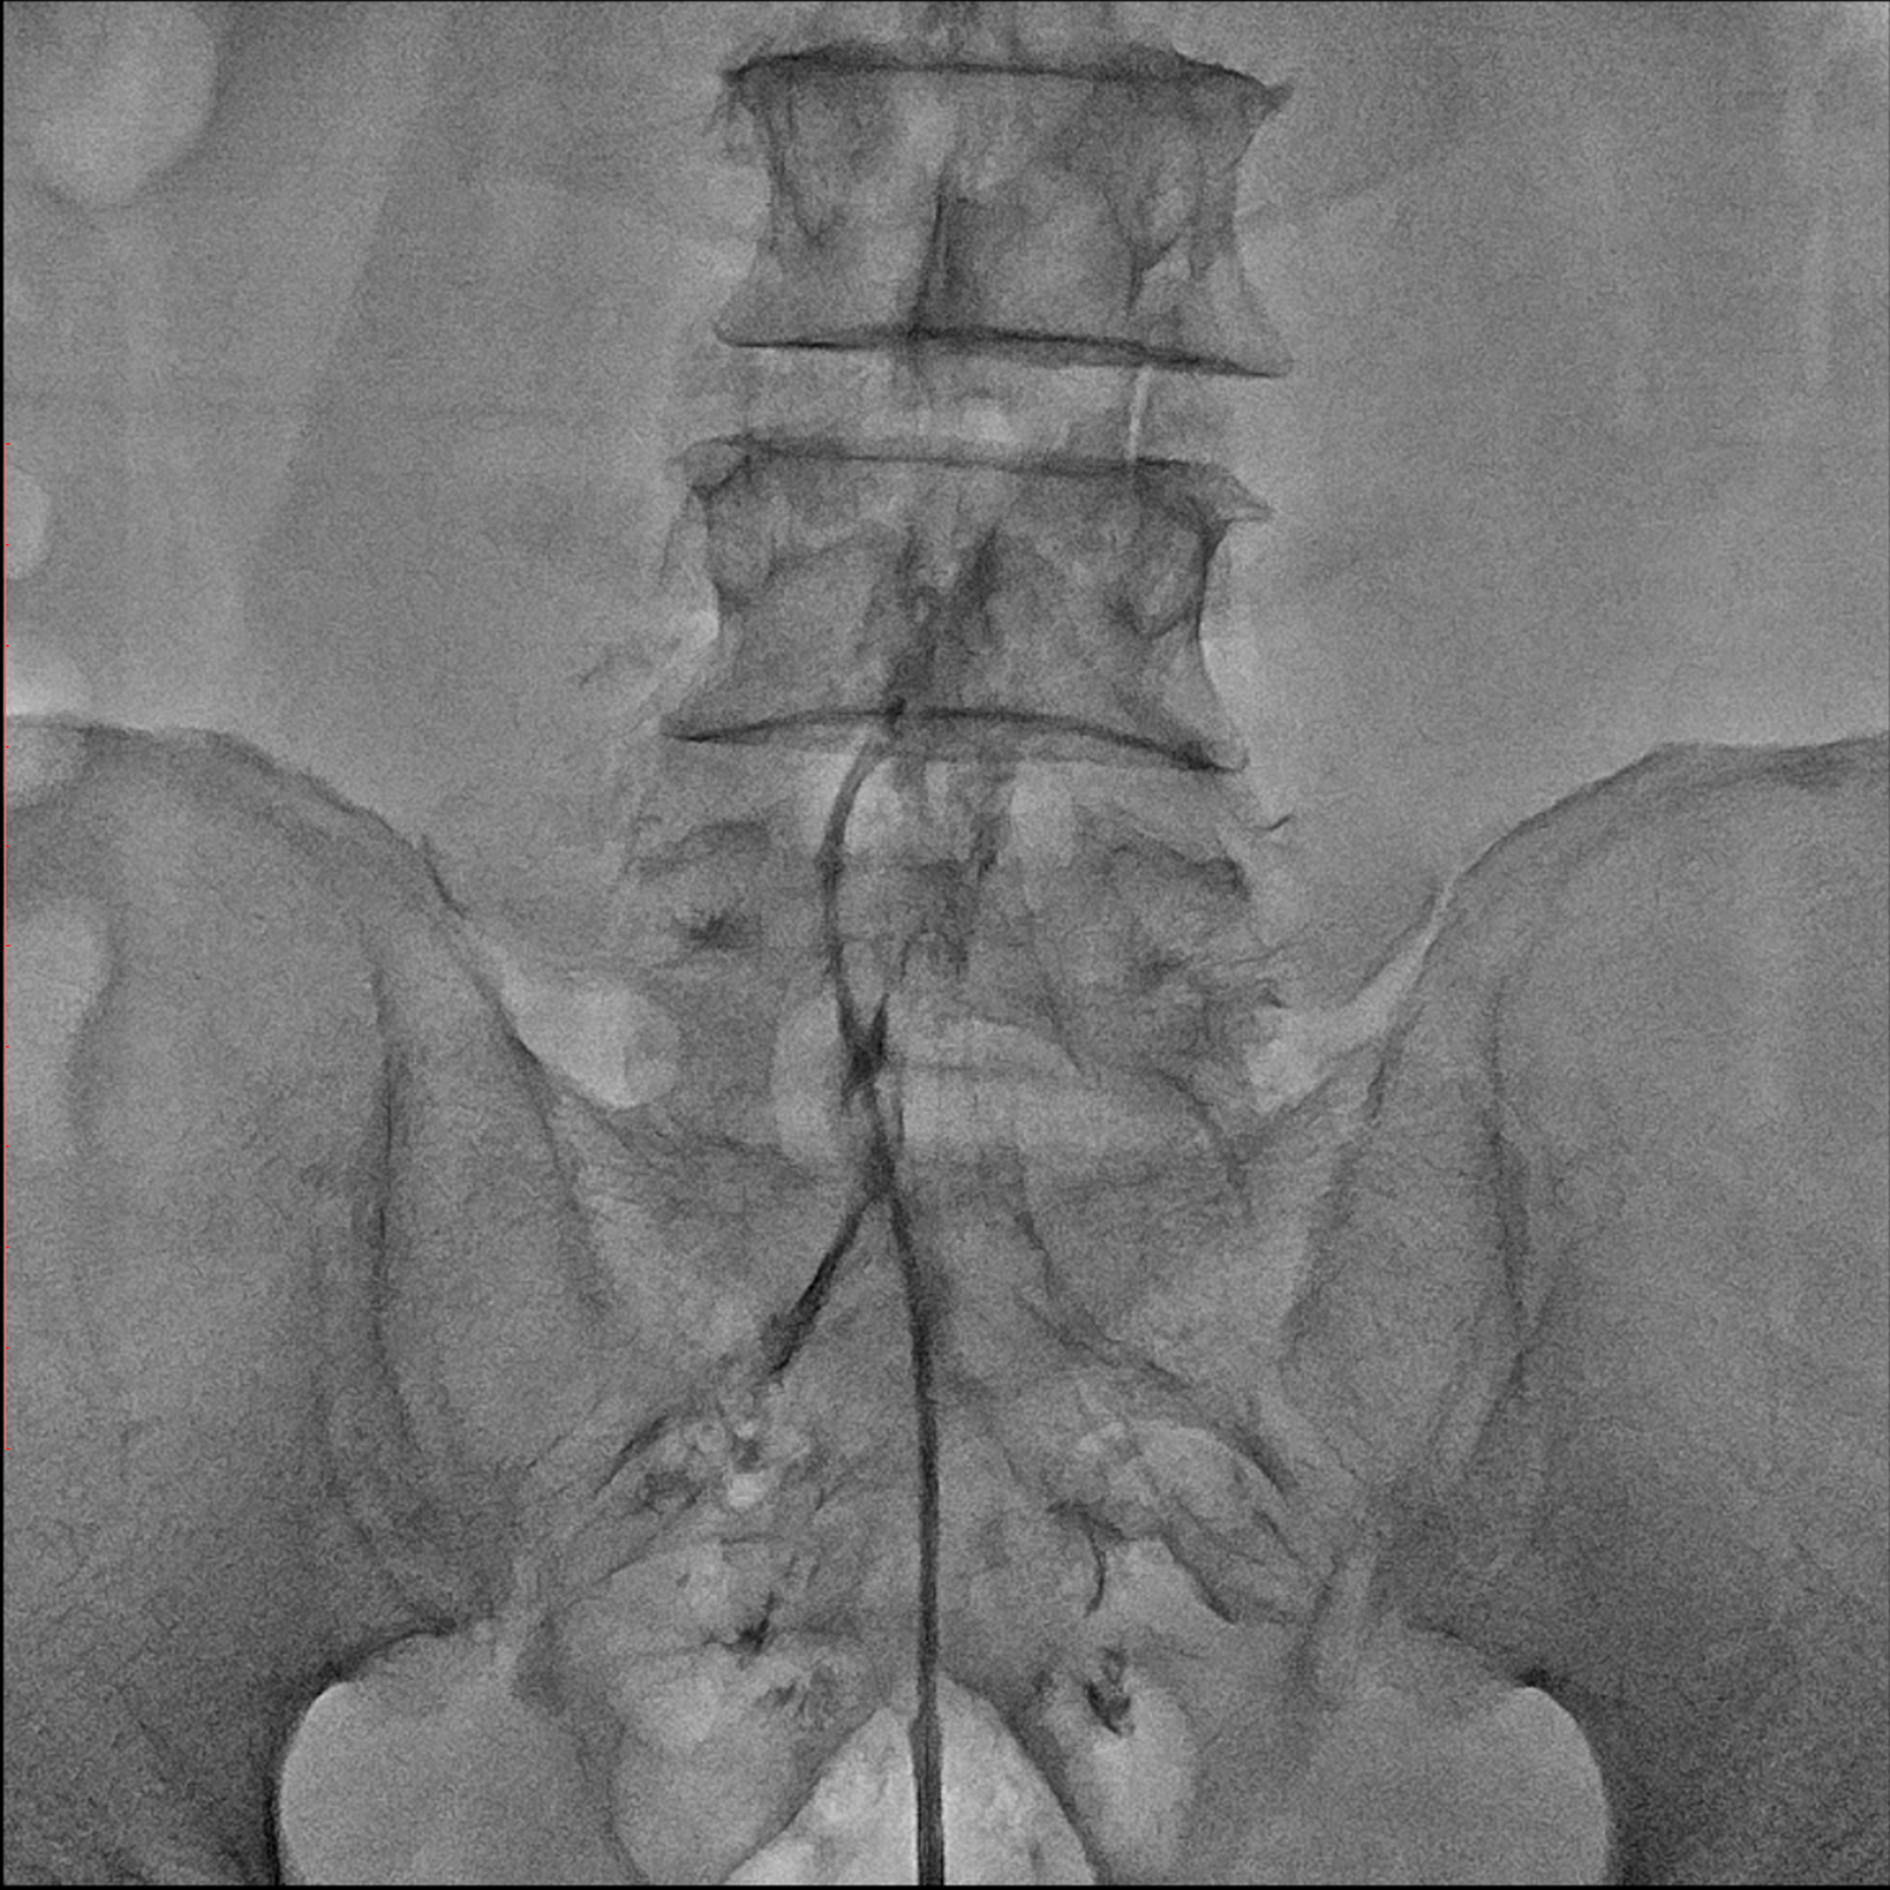

경막외 유착박리술, Epidural Neuroplasty